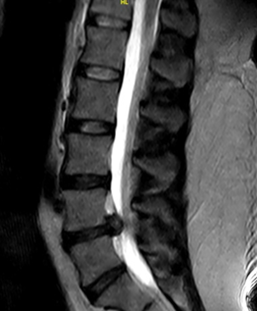

様々な部位や疾患の検査において幅広い診断情報を得るために、当院では整形外科の検査に特化した最新のオープン型MRIを導入しております。

X線一般撮影では判別しづらい骨折や骨のダメージ、靭帯など軟部組織の精査が可能です。

背骨や関節の検査に特化したMRIです。独自開発された患部ごとに対応した高感度専用コイル(体内からの信号を受信するアンテナ)と最新の画像技術により、超電導型にせまる高画質を実現しています。